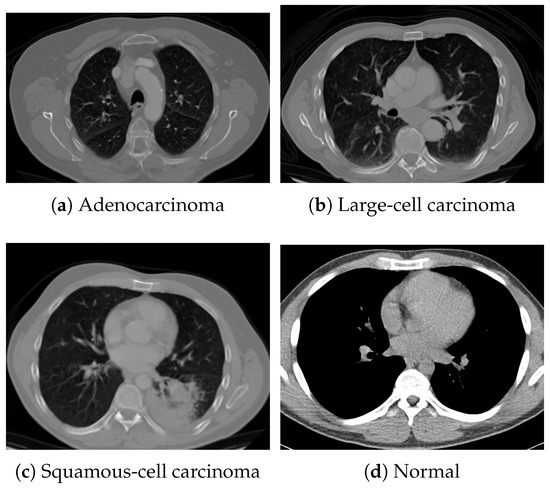

For pretraining, we utilized a subset of the J-MID (https://www.radiology.jp/j-mid/ (accessed on 6 April 2025)) database, which contains large-scale CT scans from Japanese medical institutions, and the RICORD dataset [58], an open dataset that was developed collaboratively by the Radiological Society of North America and international partners and contains chest CT scans collected from four countries. Each dataset was constructed with two domains based on mediastinal and lung window settings in chest CT images. Both domains are denoted as and , and the labels are not used during pretraining. Specifically, for the J-MID subset, (the mediastinal window) contains 31,256 CT images, and (the lung window) contains 26,403 CT images. The RICORD dataset comprises 12,897 (mediastinal window) images and 11,668 (lung window) images for pretraining. For the J-MID dataset, was generated using a window level (WL) of HU and a window width (WW) of HU, whereas was generated using a WL of HU and a WW of HU. For the RICORD dataset, was generated with a WL of HU and a WW of HU, while was generated with a WL of HU and a WW of HU. These parameter ranges were selected to cover clinically standard lung and mediastinal window settings while accommodating inter-scan variability in DICOM metadata. The corresponding images for each example are shown in Figure 2 and Figure 3. For fine-tuning and evaluation, we utilized two public datasets: the SARS-CoV-2 CT-Scan Dataset [59] and the Chest CT-Scan Images Dataset (https://www.kaggle.com/datasets/mohamedhanyyy/chest-ctscan-images (accessed on 6 April 2025)). Both datasets were used for the coronavirus disease 2019 (COVID-19) and chest cancer classification tasks, respectively. The data breakdown is as follows: the SARS-CoV-2 CT-Scan Dataset comprises 1589 training, 397 validation, and 495 test images, labeled into two (COVID-19 and Normal) classes. The Chest CT-Scan Images Dataset comprises 490 training, 123 validation, and 315 test images labeled into four (adenocarcinoma, large-cell carcinoma, squamous-cell carcinoma, and normal) classes. COVID-19 classification and lung cancer classification were selected as downstream tasks because chest CT is widely used in clinical practice for diagnosing both COVID-19 and lung cancer, allowing for an evaluation that closely reflects real-world clinical scenarios. Accordingly, to ensure reproducibility and enable fair comparisons with prior studies, we prioritized the use of publicly available datasets. The corresponding images for each example are shown in Figure 4 and Figure 5.

Figure 4.

Examples of chest CT images on the SARS-CoV-2 CT-Scan dataset: (a) COVID-19 and (b) Normal.

Figure 5.

Examples of chest CT images from the Chest CT-Scan Images dataset: (a) adenocarcinoma, (b) large-cell carcinoma, (c) squamous-cell carcinoma, and (d) normal.